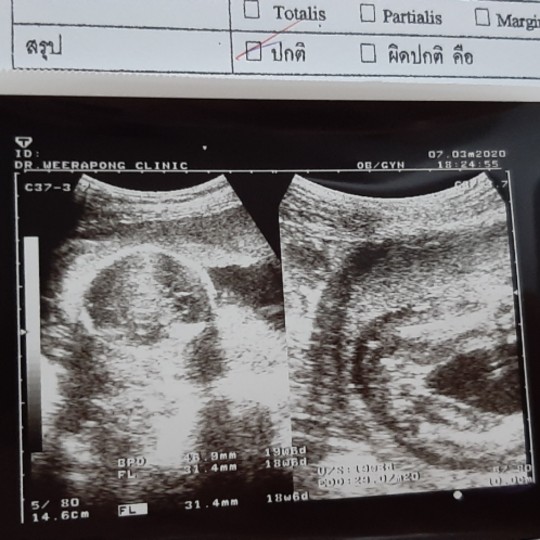

ใบซาวด์

ขอดูใบซาวด์เเม่ๆคลอดเดือนก.คหน่อยค่ะได้ผญหรือผชกันค่ะ

ชายค่ะ 15 ก.ค

ชายค่ะ15ก.ค.